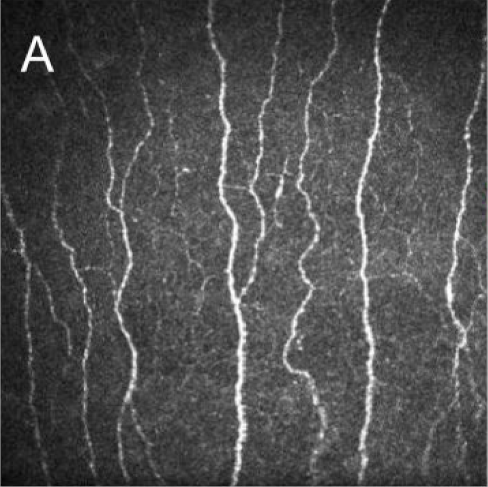

🔬 Corneal Nerve Damage Comparison

Nerve density never recovers to normal levels after LASIK. Compare the healthy, richly innervated cornea before LASIK with the permanently damaged nerve network after surgery.